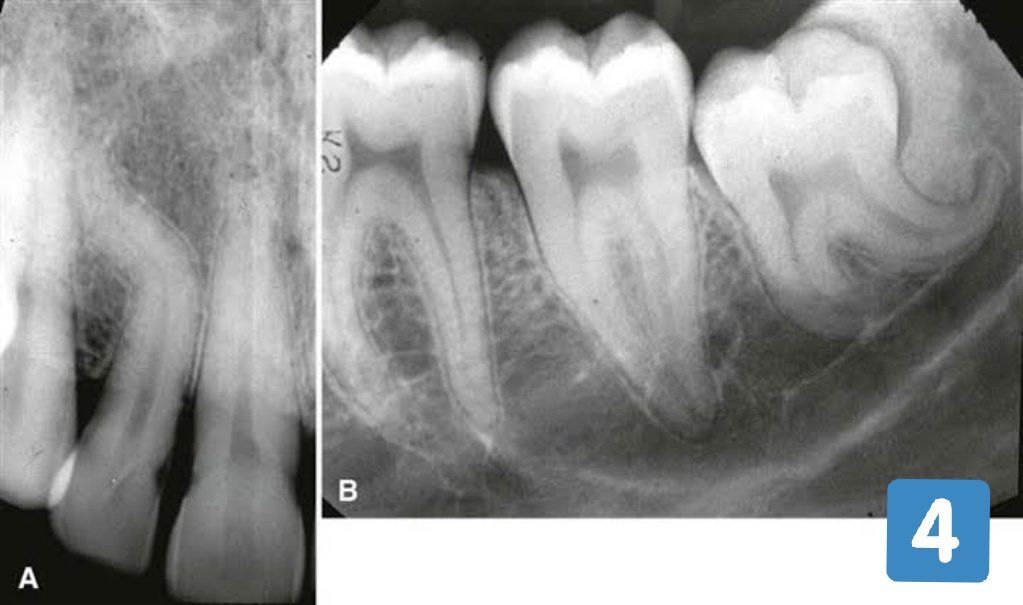

Загнутыми корень

Загнутыми корень 136 фотографий